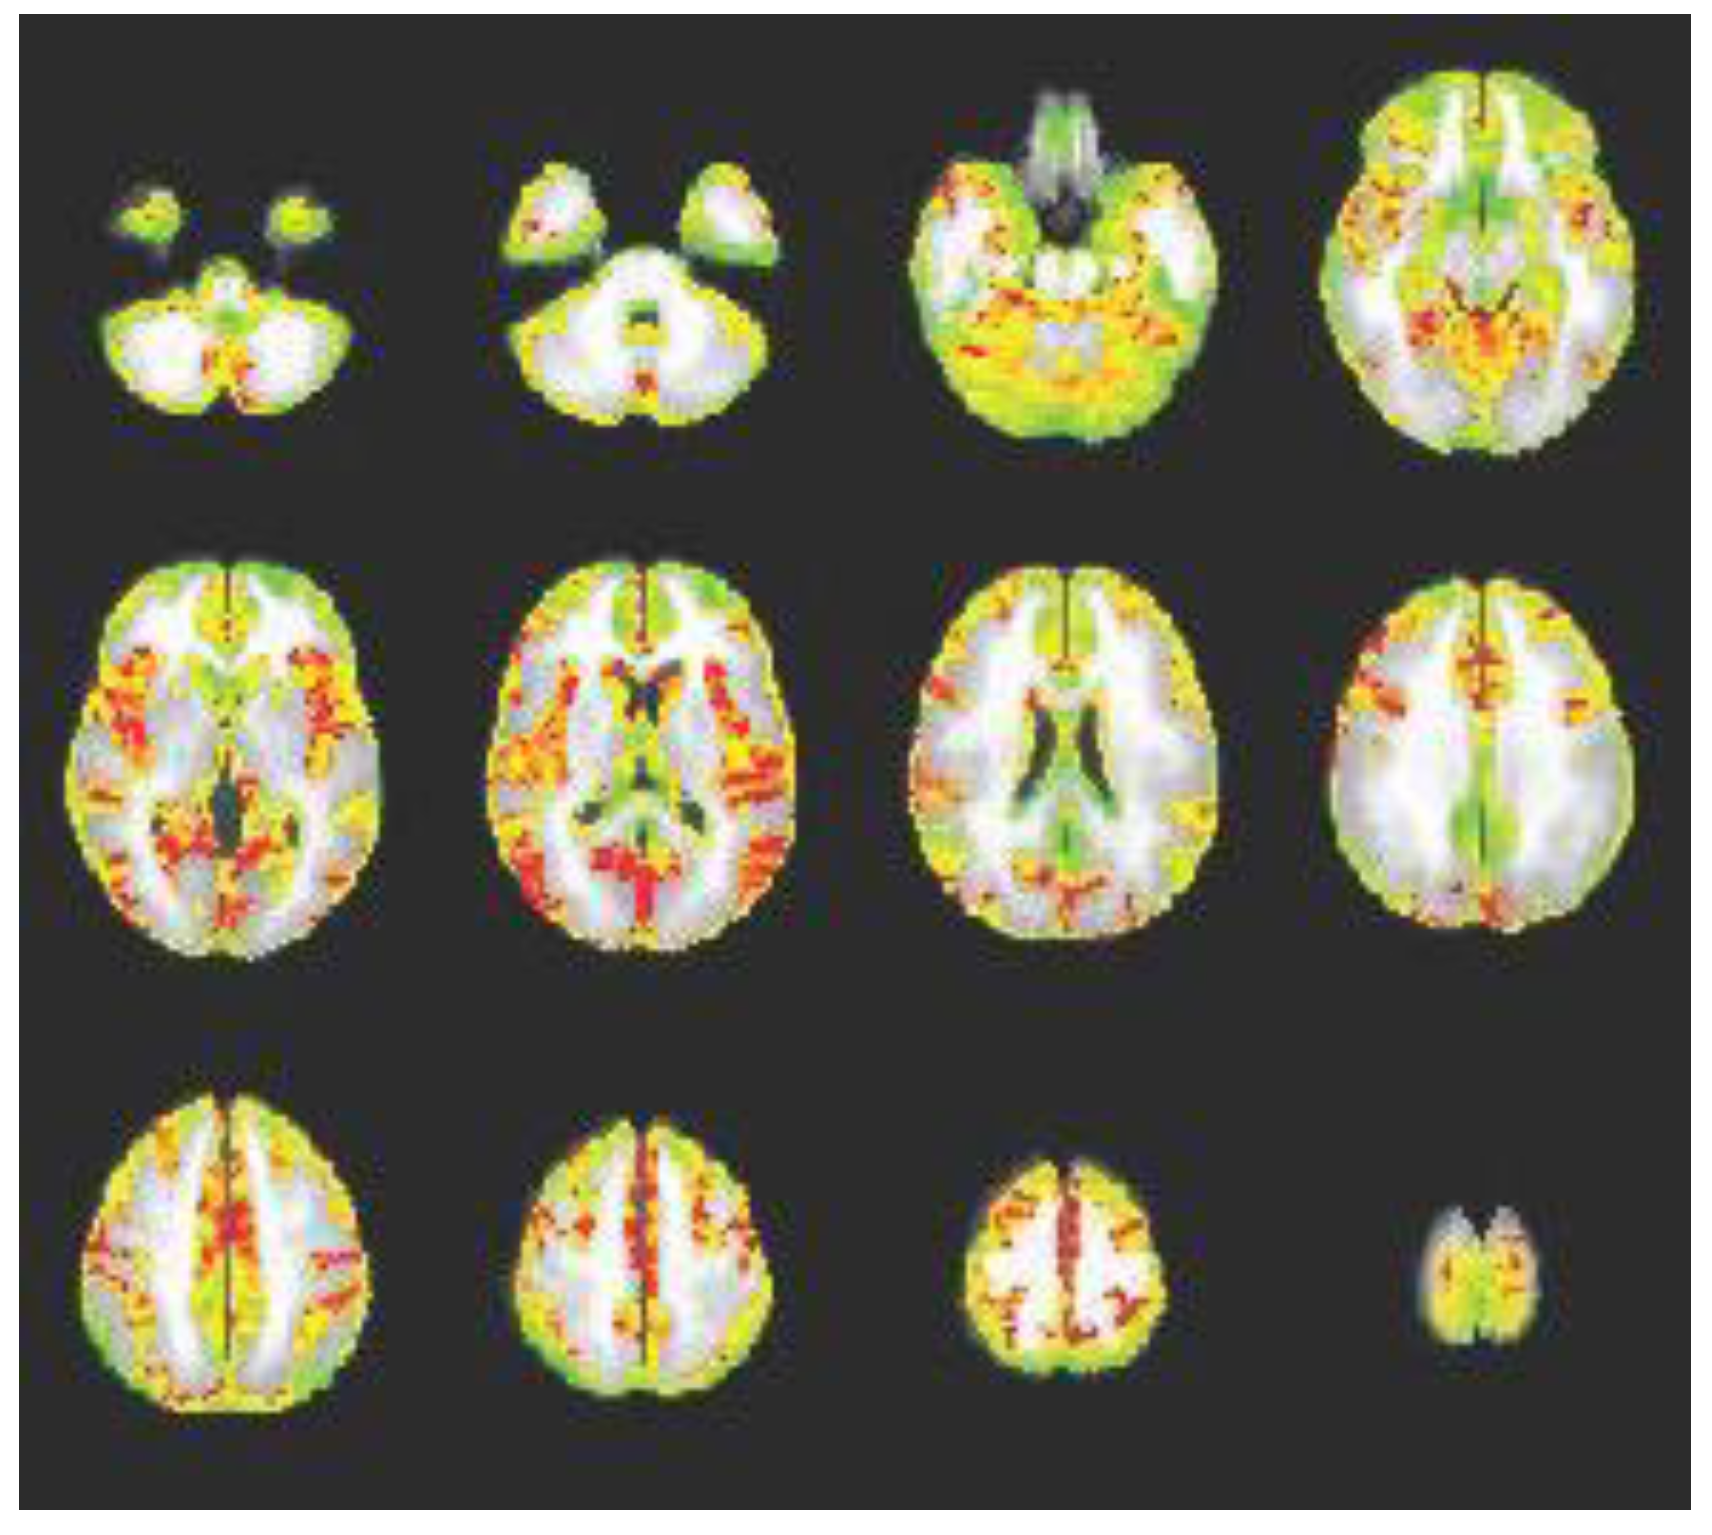

Another feasibility objective was to use individual rs-fMRI scans to produce a valid group-based motor connectivity map from the precentral gyrus (i.e., primary motor cortex) seed. In particular, the connectivity map should show graded patterns of activity rather than random pixelation. To produce this map, AFNI’s 3dDeconvolve tool was used. A general linear model (GLM) was applied to each participant’s co-registered functional images (ignoring censored values). The GLM analysis incorporated covariates accounting for linear, quadratic, cubic, and quartic drift and six motion parameters, as well as the seed (precentral gyrus) time series. AFNI’s 3dttest++ function was then used to produce seed-based connectivity maps. The validity of this map was judged qualitatively.

Group-Based Connectivity Map: The group connectivity map was deemed a valid connectivity map, as connectivity (red areas) can be observed between the precentral gyrus and multiple other brain areas that are associated with motor function: bilateral insula, superior parietal lobule, paracentral lobule, posterior cingulate, superior and middle prefrontal areas, occipital areas, and cerebellar areas; see Figure 4. Importantly, the pattern is graded, showing transitional areas of connection rather than random pixelation; transitional areas of connection are indicative of strong functional connections.

Figure 4. Group Seed-Connectivity Map for Precentral Gyrus. This figure depicts group-level connectivity between the precentral gyrus and multiple brain regions (in red). Importantly, the pattern is graded, showing transitional areas of connection rather than random pixelation.